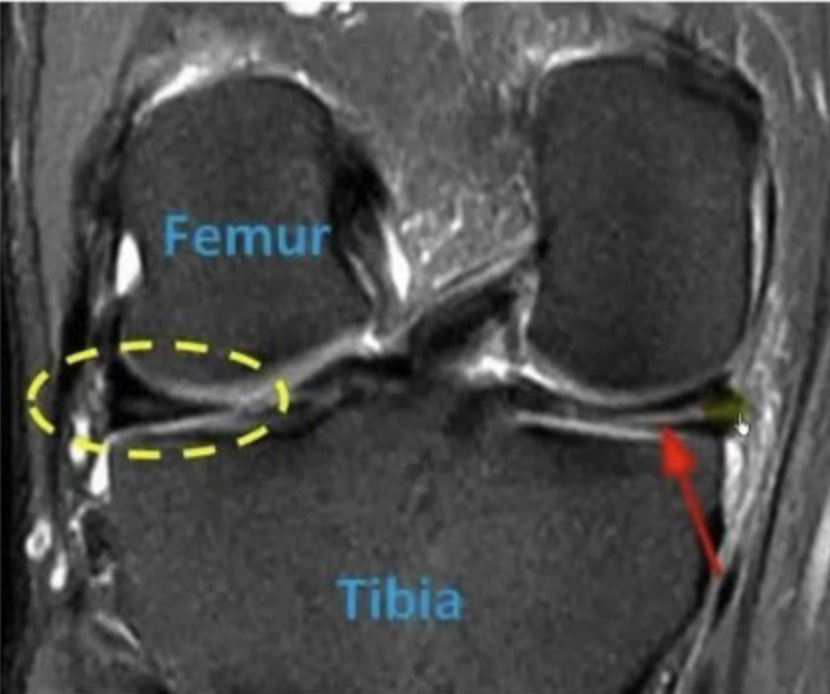

Οι μηνίσκοι λειτουργούν ως «αμορτισέρ» ανάμεσα στο μηριαίο και την κνήμη. Η ρήξη μηνίσκου μπορεί να προκληθεί από αθλητικό τραυματισμό ή εκφυλιστικές αλλοιώσεις.

Οι πλάγιοι σύνδεσμοι προσφέρουν σταθερότητα στο γόνατο και τραυματίζονται συχνά σε αθλήματα επαφής.